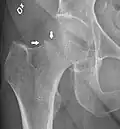

Fracture (black arrow, pertrochanteric) versus a skin fold (white arrow).